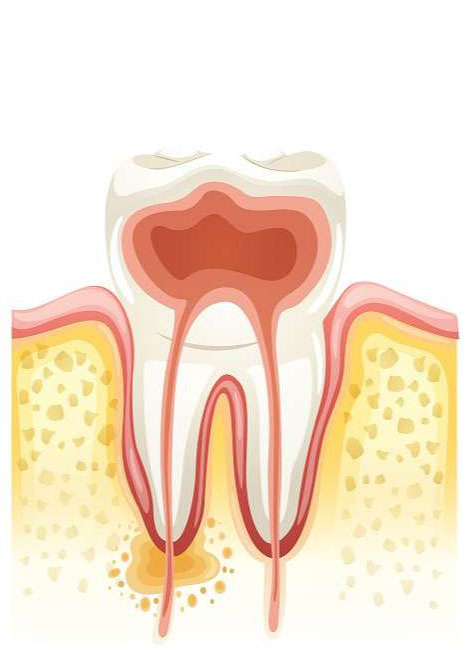

Es un tratamiento que realizamos en el interior del diente. La pulpa dentaria (nervios y vasos) tiene una misión clave en el momento precoz de la formación de los dientes, pues aporta los nutrientes necesarios para el desarrollo completo de los mismos.

Una vez producido el cierre de la raíz termina el proceso de crecimiento del diente.

A partir de este momento la pulpa tiene menos importancia, pero aún conserva algunas funciones, como son el aporte hídrico al diente que mejora sus propiedades físicas y mantener la sensibilidad dental (si esta desapareciera por completo los dientes se romperían y no nos daríamos cuenta, o sea, actúa como una “alama” en este sentido).